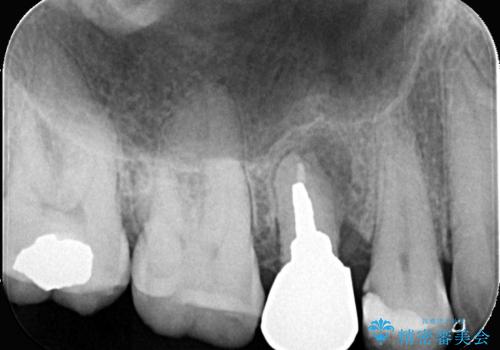

右上5番が根尖性歯周炎と歯周病が同時に併発しており、骨が大きく溶け、歯の動揺も著しかったため保存困難と判断をし抜歯してインプラントで治療を行いました。

インプラントはインプラント周囲炎になりにくいスクリュータイプを使用しています。

右上4番は虫歯になっていたので、虫歯を除去後、セラッミクインレーで治療を行いました。

従来のインプラント治療では、オペを二回に分けることが主流でしたが今は1回のオペで治療を終える事が出来るようになりました。

インプラントと骨が強度にくっつくように骨密度を上げながらドリリングを行っているのと、患者様の骨の状態に合わせてインプラントの形態を選ぶことで可能となっています。